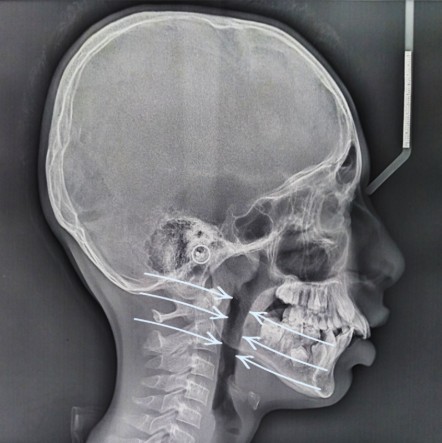

Face growth in children is not just genetic β it is guided by breathing, posture and airway function. The way a child breathes influences jaw development, facial structure and long-term airway health.

Mouth breathing, poor tongue posture and disturbed sleep can gradually alter facial growth direction β leading to narrower jaws, reduced airway space and changes in facial balance.

Breathing patterns influence not just the face β but the nose, airway, jaw and posture over time.